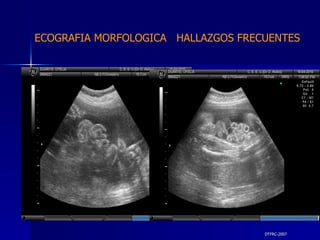

DTFRC-2007 ECOGRAFIA MORFOLOGICA  HALLAZGOS FRECUENTES   OTROS HIGROMA QUISTICO  2 ENFERMEDAD ADENOMATOSA PULMONAR  1 ARTERIA UMBILICAL UNICA  2 HIDROPS FETAL NO INMUNE  1 QUISTE DE CORDON UMBILICAL  1 ALTERACION DE LIQUIDO ANMIOTICO  2 SINDROME TRAFUSIONAL FETO FETAL 1 LABIO LEPORINO  2 TOTAL  12  42 %

DTFRC-2007 ECOGRAFIA MORFOLOGICA  HALLAZGOS FRECUENTES   GESTACIONES MULTIPLES  N 211 SINDROME TRANSFUCIONAL FETO FETAL (15/20 )